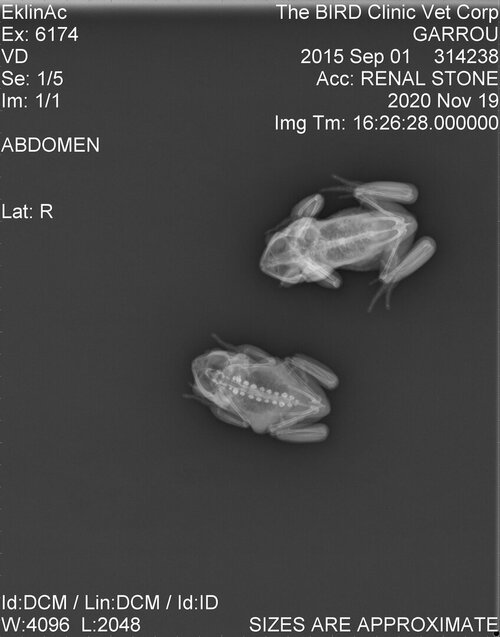

Not exactly like this. BUT you can see below what was discovered in some diagnostic rads of my monkey frogs (one had a bladder stone, so we radiographed all of them). You can see the frog at the bottom has-bilateral, calcified bumps-along the spine. They did not show through the skin but a frog carries more fat on their back than a cham. This is a completely asymptomatic, healthy frog and 2 of the 12 had this. I suspect it is something that happens developmentally in the egg, or in the frog case, tadpole stage. In general, the more a problem is bilateral the less likely it is to be something problematic.